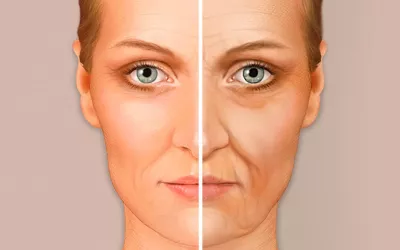

Cara de Ozempic, así envejece el rostro el adelgazante de moda

La Ozempic face es un efecto estético colateral del uso del conocido fármaco para adelgazar que se produce por la pérdida de grasa facial asociada a la rápida disminución de peso y que provoca una apariencia envejecida del rostro. Te decimos cómo prevenirlo. -